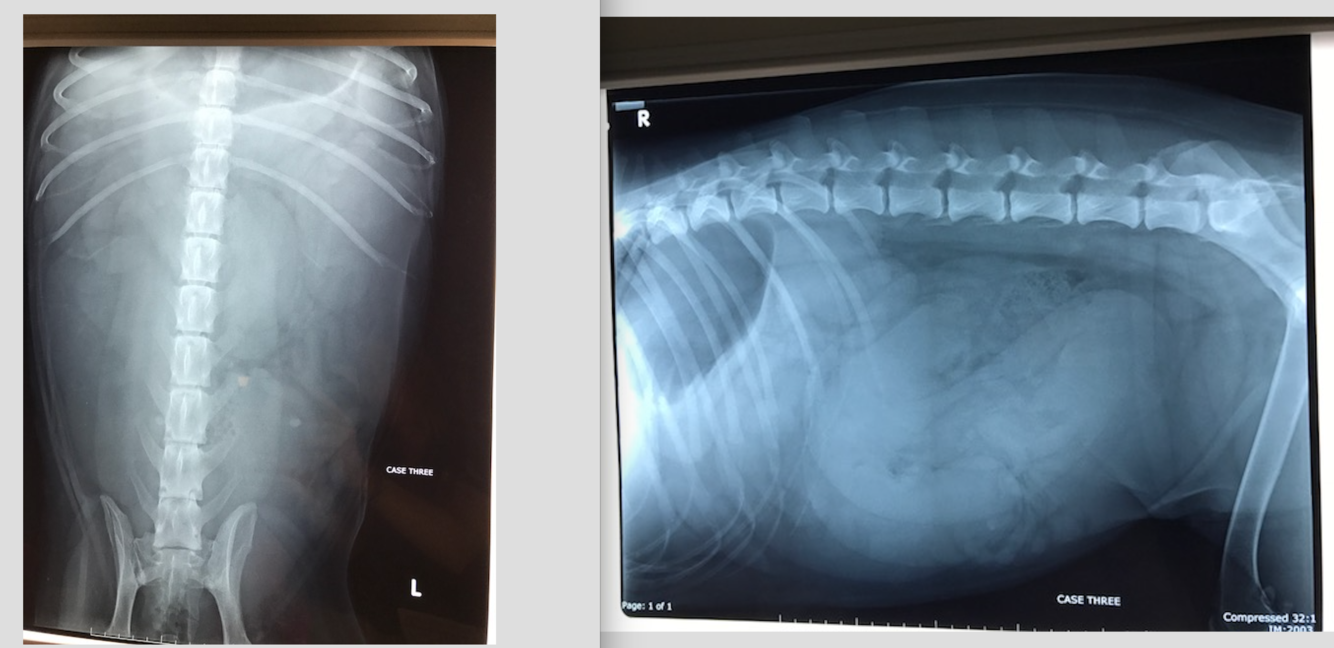

Layla 4 yo FS JRT

Vomiting and diarrhoea for 3 days

HR 120 MM pink to very pink CRT 1 sec, tacky

Pulses normal and synchcronous, auscultation

What are the types of ileus?- Which type is present in Layla?

How might you further investigate her diarrhoea and vomiting?

Oscar 12 yo MN DLH

Hx: Vocalised and collapsed at home

CE: Systolic heart murmur, increased RR. Pale gums, tense abdomen with mass lesion palpable cranially.

Large irregularly margined mass within the cranioventral abdomen– which is the most likely organ of origin for this mass?

The mineralised opacity caudal to this mass- what is it called?

2-3 x the length of L2 for cats.

2.5-3.5 the length of L2 for dogs.

Hepatocellular Carcinoma